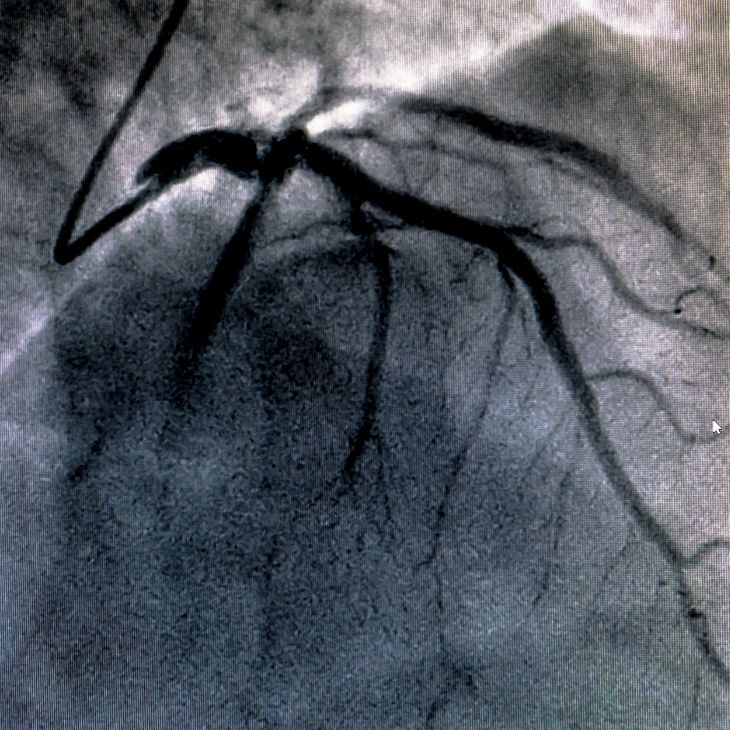

Coronary angiography is a gold-standard test used to visualise the heart’s arteries and detect blockages or narrowing. As a leading consultant cardiologist and internationally recognised expert in coronary physiology, I use advanced techniques to deliver accurate, minimally invasive diagnosis.

During the procedure, a thin catheter is inserted into the wrist or groin and guided to the heart. Contrast dye is injected, and X-ray images reveal the condition of the coronary arteries. This procedure helps determine the best treatment – such as stenting or bypass surgery. Performed under local anaesthetic, most patients return home the same day.